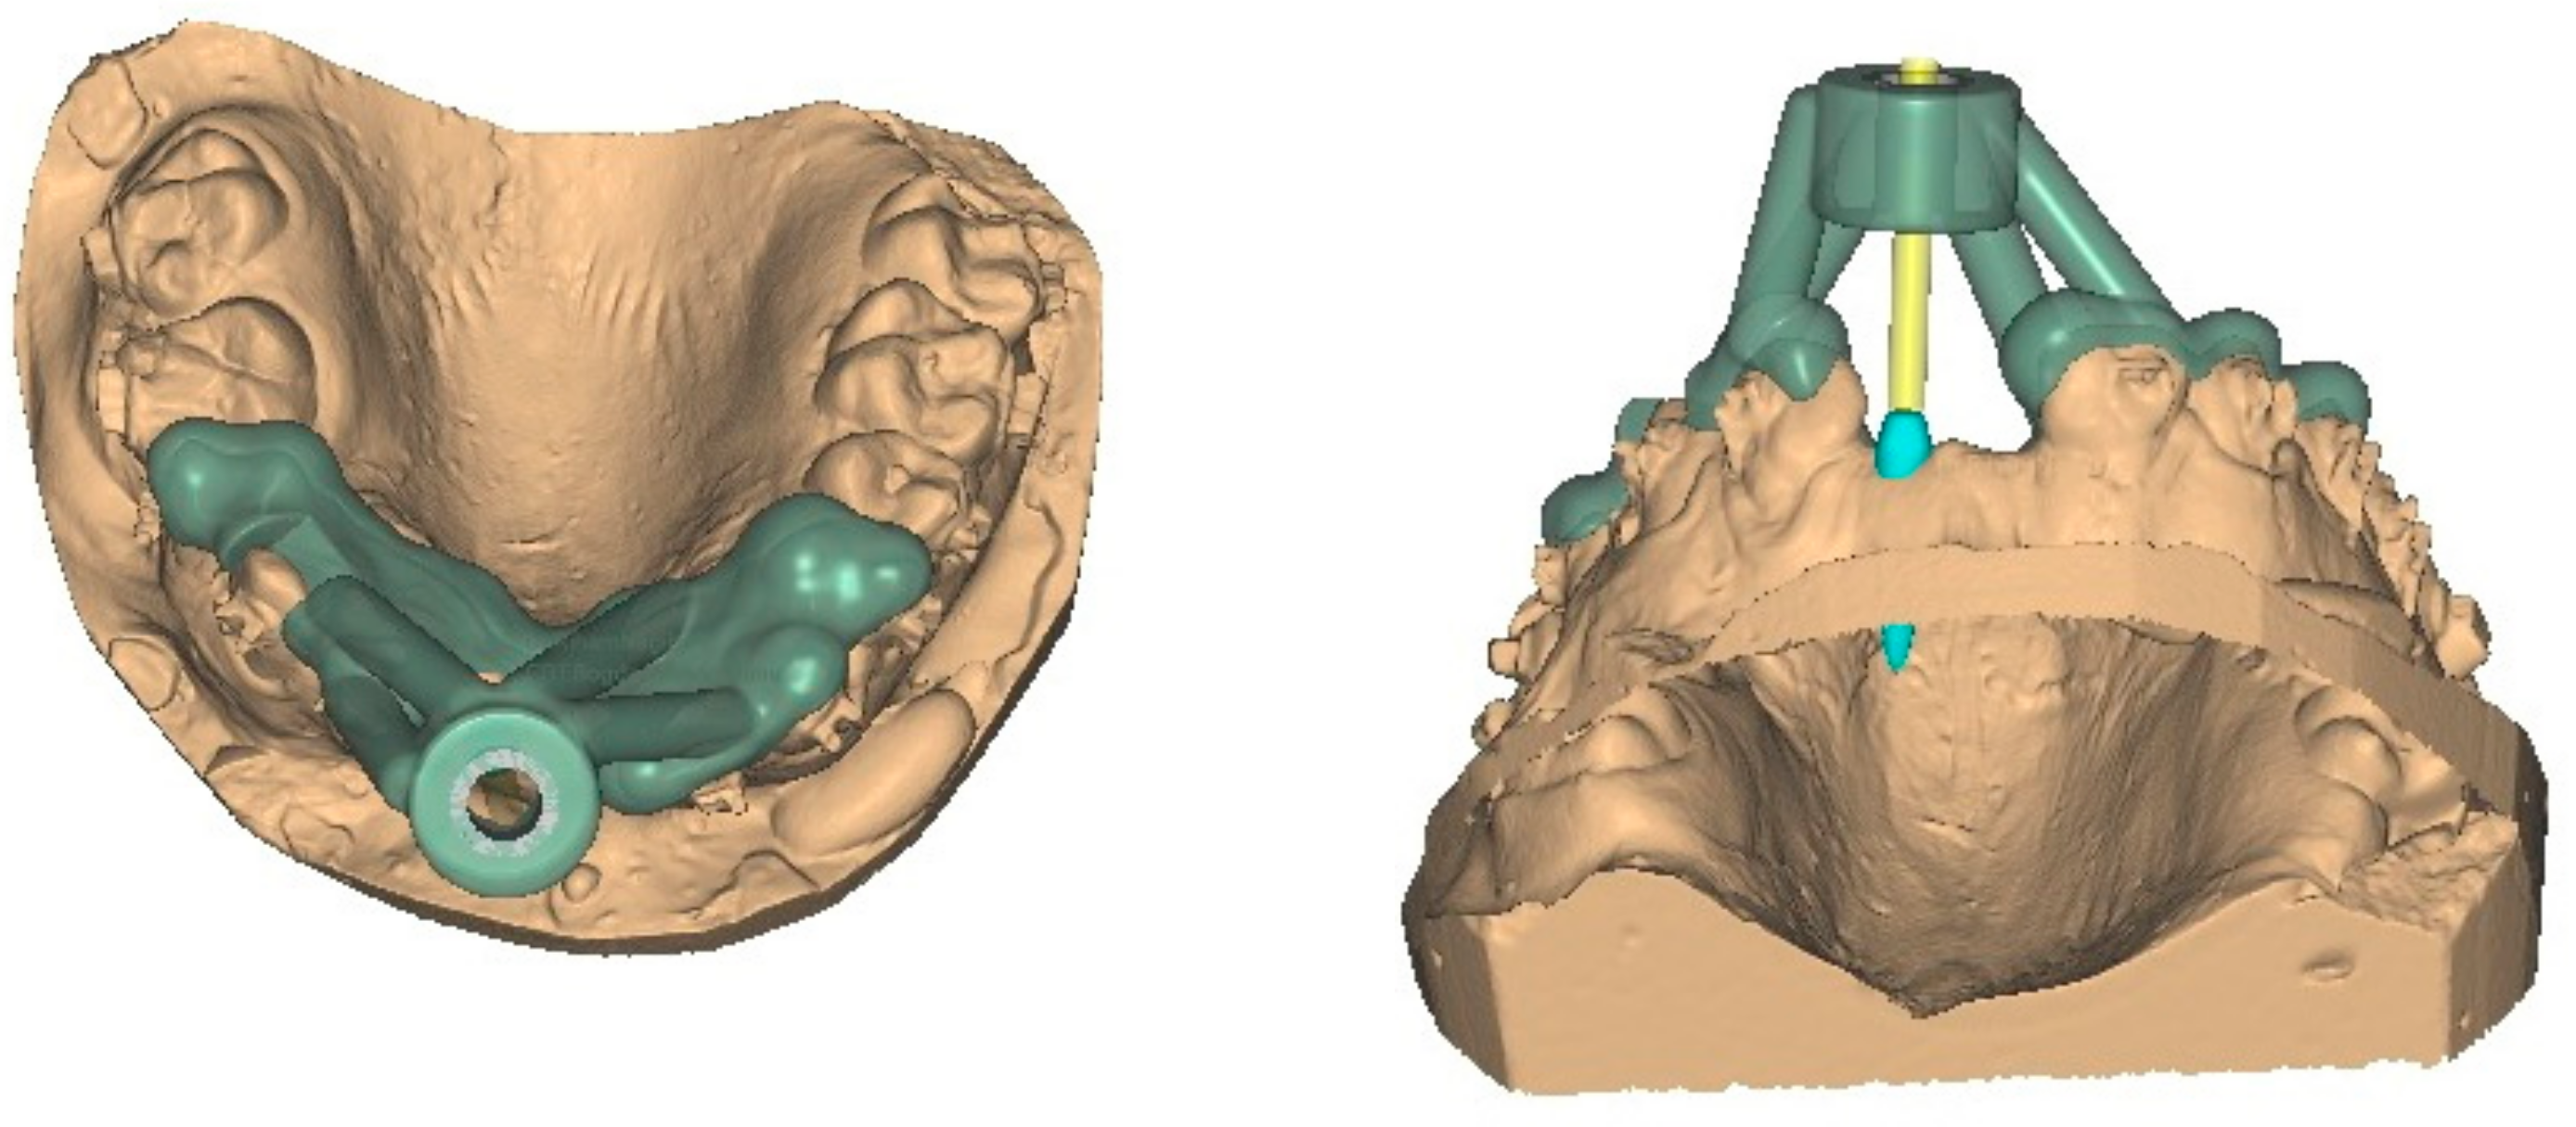

2.2. Computer Aided TAD Insertion Guide Design

2.3. Finite Element Analysis of Individualized TAD Insertion Guide